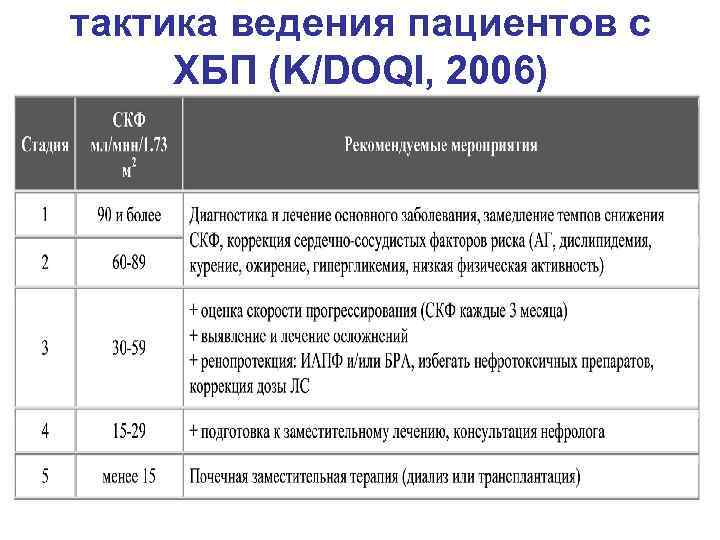

тактика ведения пациентов с ХБП (K/DOQI, 2006)

тактика ведения пациентов с ХБП (K/DOQI, 2006)